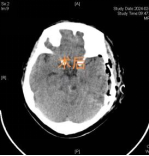

术后复查:病灶完整切除

各项复查显示,病灶已被完整切除、颅神经功能均未受损。陈女士右侧肢体感觉和运动功能得到明显改善,她阴郁的脸上终于露出了久违的笑容。